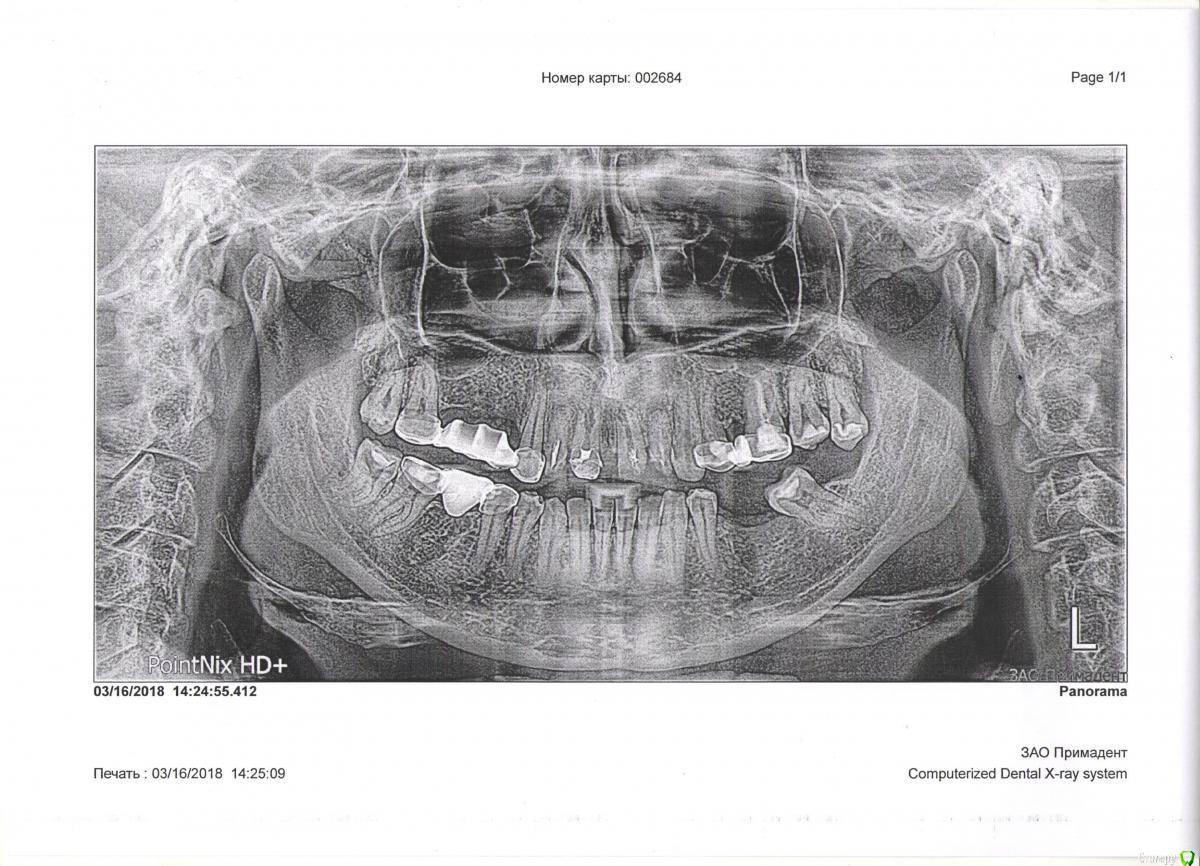

Natalyk Опубликовано 19 марта, 2018 Поделиться Опубликовано 19 марта, 2018 Доброго дня,подскажите,что лечит,что удалять,хочу заменить мосты на эстетичные,возможны ли металлокерамика мосты? Ссылка на комментарий

red_butler Опубликовано 19 марта, 2018 Поделиться Опубликовано 19 марта, 2018 Удалить зубы мудрости, заменить мосты на одиночные коронки, области отсутствующих зубов имплантировать. Прогноз резцов на верхней челюсти плохой. хочу заменить мосты на эстетичные,возможны ли металлокерамика мосты? металлокерамика не самое эстетическое решение... Ссылка на комментарий

Natalyk Опубликовано 26 марта, 2018 Автор Поделиться Опубликовано 26 марта, 2018 (изменено) понимаю,что не лучший выбор ,подскажите ставить металлокерамику мост ,при удалении 12 по 22 мост?1. 17 по 262. 2 моста 17 по 23 и 24 по 26 какой вариант выбрать? Изменено 26 марта, 2018 пользователем Natalyk Ссылка на комментарий

red_butler Опубликовано 26 марта, 2018 Поделиться Опубликовано 26 марта, 2018 какой вариант выбрать? Имплантацию не рассматриваете? Ссылка на комментарий

Natalyk Опубликовано 27 марта, 2018 Автор Поделиться Опубликовано 27 марта, 2018 Имплантацию не рассматриваете? не могу решиться на это морально и физ.,нет доверия,не везет наверное мне,хотя всегда иду осознанно к врачу.,если металлокерамика ,то потеря своих зубов через несколько лет,или же он (мост,мосты)не будет держаться?,мне 45лет Ссылка на комментарий